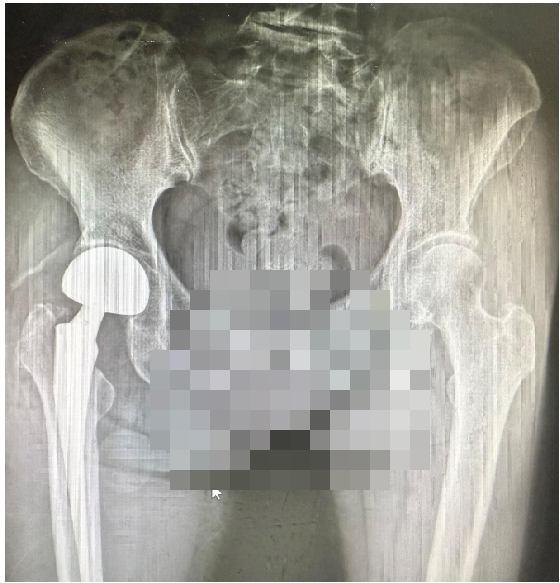

近日,南方醫(yī)院創(chuàng)傷骨科髖關(guān)節(jié)外科胡稷杰主任醫(yī)師團隊與麻醉手術(shù)中心劉衛(wèi)鋒副主任及護理團隊通力協(xié)作,成功為一名78歲股骨頸骨折高齡患者實施神經(jīng)阻滯麻醉聯(lián)合鎮(zhèn)靜鎮(zhèn)痛技術(shù)DAA入路股骨頭置換術(shù)。手術(shù)全程僅用時30分鐘。術(shù)后患者意識清醒,在醫(yī)護人員指導(dǎo)與保護下自主行走離開手術(shù)室,患者及家屬對治療效果高度滿意。

手術(shù)當(dāng)天,麻醉手術(shù)中心劉衛(wèi)鋒副主任團隊實施精準(zhǔn)神經(jīng)阻滯麻醉聯(lián)合鎮(zhèn)靜鎮(zhèn)痛,全程保留患者意識及自主呼吸。胡稷杰主任醫(yī)師與李凱群主治醫(yī)師合作,經(jīng)髖關(guān)節(jié)前方DAA入路,順利完成股骨頭取出與假體置入。